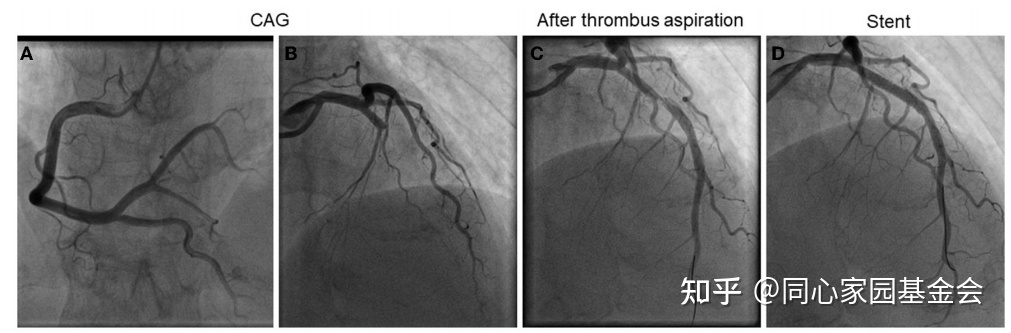

诊断为急性前壁心肌梗死,转入导管室进行急诊冠状动脉造影,示左前降支近端完全闭塞伴血栓(图2)。血栓抽吸后行血管成形术,置入了一枚药物洗脱支架(3 × 18mm)。患者在PCI期间接受普通肝素(6,000 IU)治疗,并给予双联抗血小板治疗【阿司匹林(100 mg/天)和氯吡格雷(75 mg/天)】。

图2:急诊冠状动脉造影和PCI:(A)右冠状动脉;(B)左冠状动脉:(C)血栓抽吸术后;(D)置入支架后。